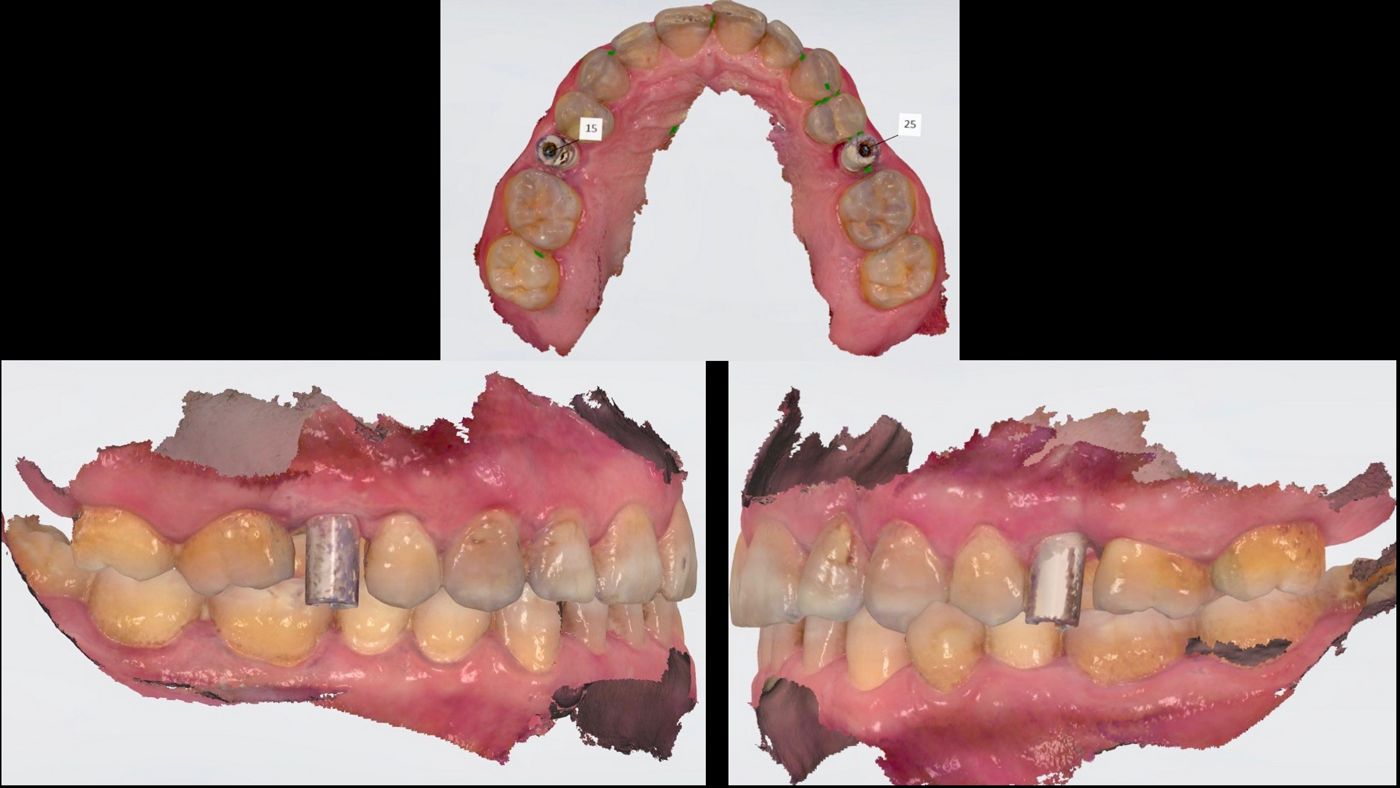

Due to the systemic and local healthy situation, the immediate protocol was planned. Clinical examination of both premolars revealed no gingival recession, adequate width and thickness of keratinized gingiva (thick biotype) (Fig. 1), a shallow probing pocket depth and no bleeding on probing. From a radiological diagnosis we confirmed an integral and thick buccal bone plate, no radiolucency at the apex, good bone availability and alignment between the roots and the alveolar crest (Figs. 2-3). After the prosthetic analyses (casts, wax-up and smile design), we proceeded to design and manufacture two provisional crowns and create a surgical stent. With all this information we planned to use two 3.75 mm x 12 mm Straumann® BLX, Roxolid®, SLActive® implants with two 2.5 mm SRAs height.

After 8 weeks of healing, the provisional crowns were unscrewed, SRAs re-tightened to 35 Ncm and final impressions taken. Ten days later, the try-in of the frameworks was done, and the colors were selected. After another ten days, final crowns were inserted and adjusted. (Figs. 9-14).